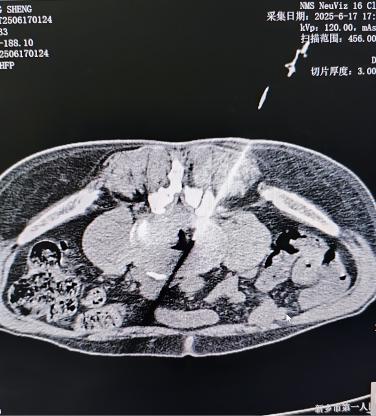

肾结石/泌尿系统问题:当结石卡在输尿管或肾脏发炎时,疼痛可剧烈放射至同侧腰肋部,常伴随血尿、排尿异常或发热。这种疼痛通常与腰部活动关系不大,却可能阵发性加剧。

其他内脏疾病:如盆腔炎、附件炎、胰腺炎、主动脉瘤、腹部占位等,有时也会以腰痛为表现,需结合其他症状综合判断。